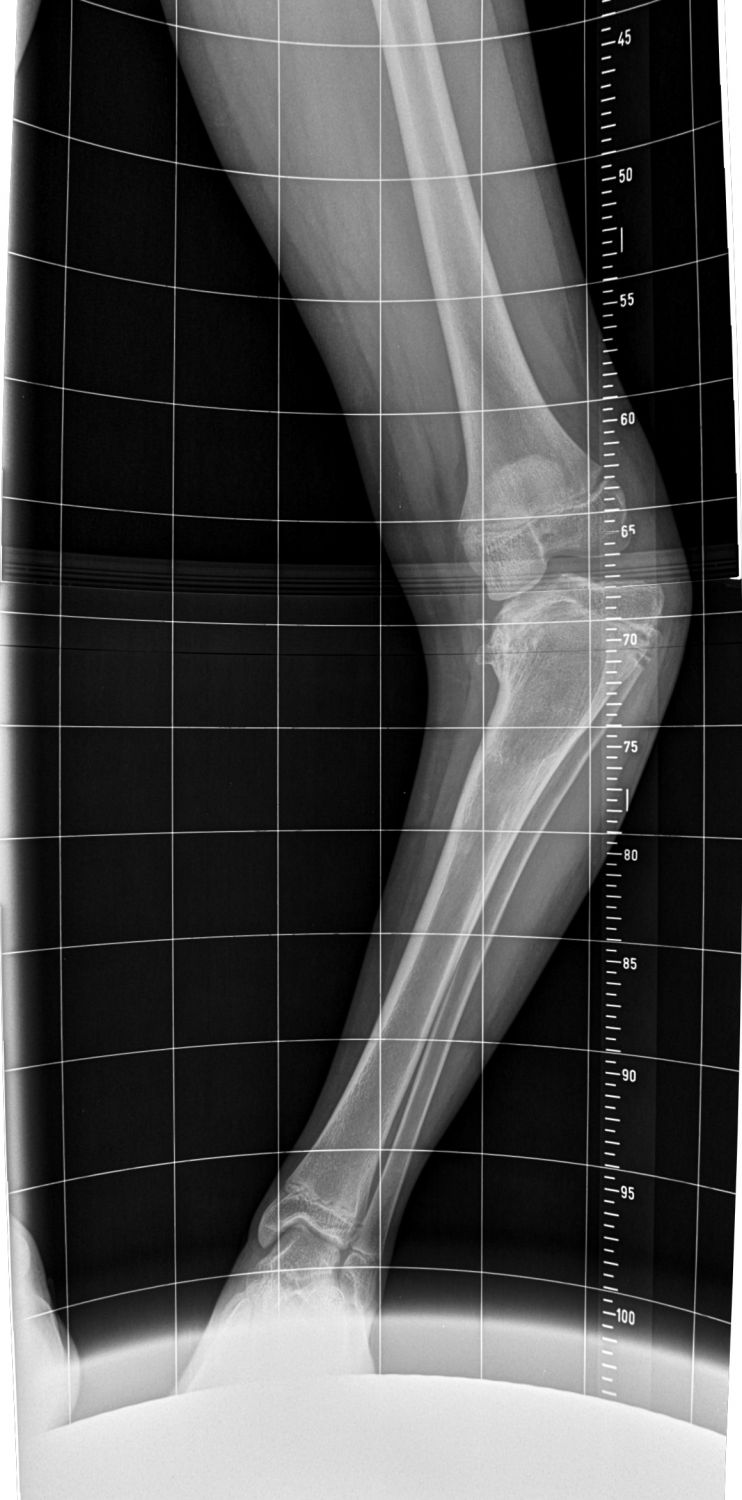

Maria leidet an Morbus Blount, einer knöchernen Wachstumsstörung im Schienbein. Betroffene entwickeln O-Beine – bei Maria sind diese extrem ausgeprägt.

Ohne Behandlung könnte das Mädchen irgendwann nicht mehr laufen. 2019 begradigten Chefärztin Christine Bollmann und ihr Team zunächst das rechte Bein und stabilisierten es mit einer Spezialplatte. Noch im gleichen Jahr folgte das linke Bein. „Wir hatten gehofft, dass sich die Wachstumsfuge erholt und Marias Beine gerade weiterwachsen. Dies hat sich leider nicht bestätigt“, so Dr. Bollmann. Mit fortschreitendem Wachstum wurden Marias Beine wieder krumm. „Hätten wir damals noch abgewartet, könnte sie heute gar nicht mehr laufen, dann wären die Knie längst kaputt.“

Diesen Herbst wurden Marias Unterschenkel erneut begradigt. In einer ersten Operation wurden eine komplexe Achskorrektur des Unterschenkels und eine Stabilisierung des Knochens durch eine Platte vorgenommen. Die Wachstumsfuge im Unterschenkel wurde dabei zusätzlich verödet werden, damit die Beine nicht noch einmal schief werden.